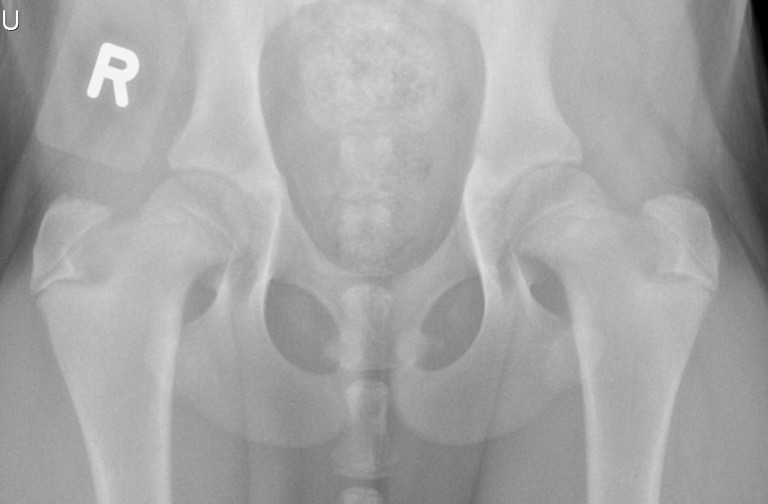

Joint Replacement Society

- Public education regarding joint replacement options, procedures, and outcomes